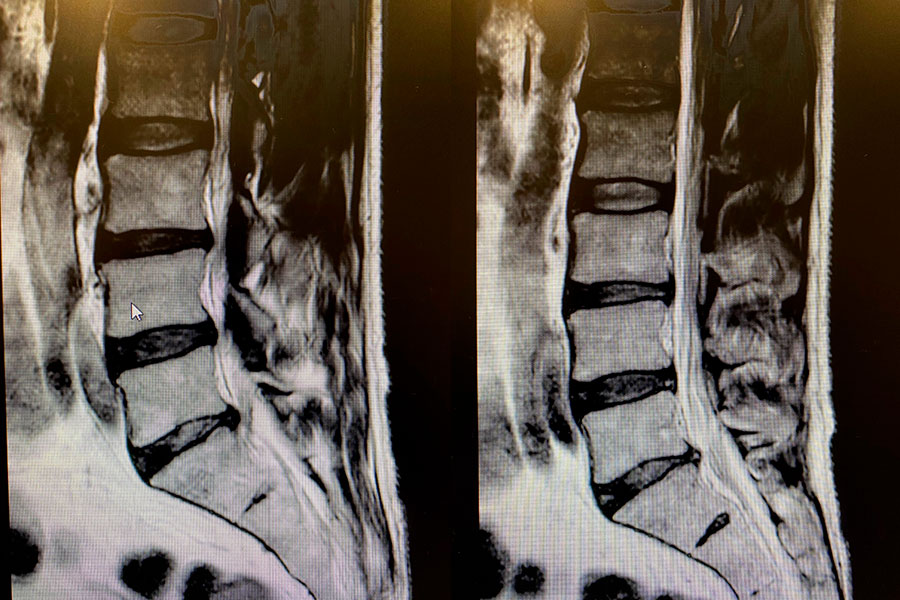

Caso clínico: endoscopia de columna multinivel L4L5 y L5S1

Los síntomas que presentaba el paciente eran dolores acentuados en las piernas, claudicación a la marcha y calambres y hormigueos en las piernas.

Durante la intervención quirúrgica, se abordarán los dos niveles mediante la técnica de endoscopia de columna.